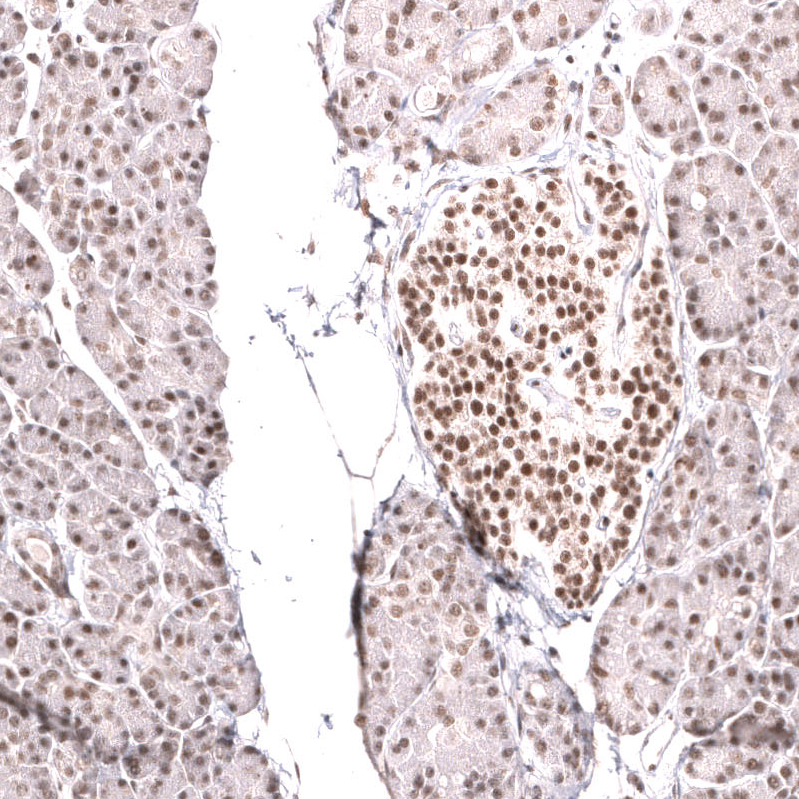

Immunohistochemical staining of human cerebral cortex shows strong nuclear positivity in neurons.